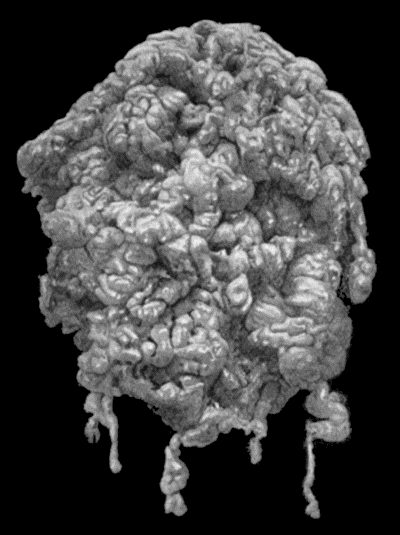

168.Multiple partially ossified Chondromas of Synovial Membrane from Shoulder-joint 542

169.Multiple Cartilaginous Loose Bodies from Knee-joint 543